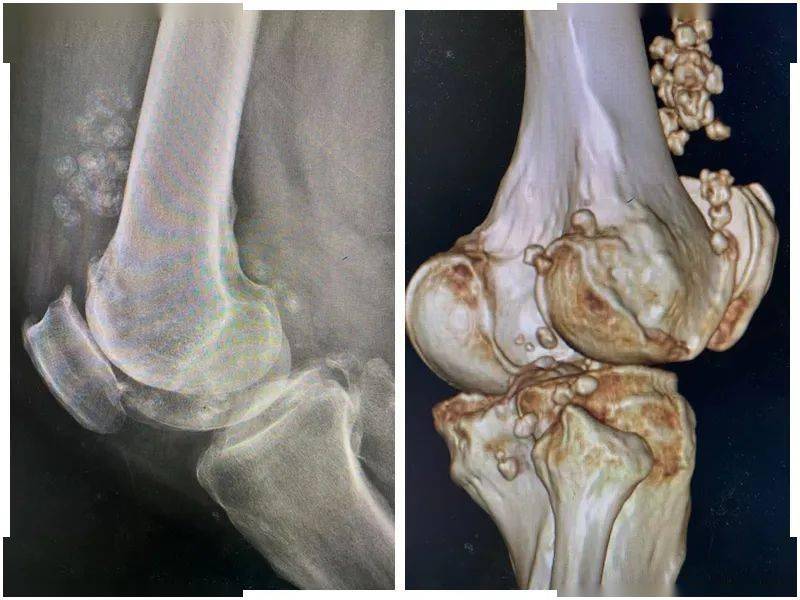

关节内的老鼠(滑膜软骨瘤)~如何诊断治疗?

一窝"小老鼠"折磨50岁大叔6年,整整36"只"!_膝关节